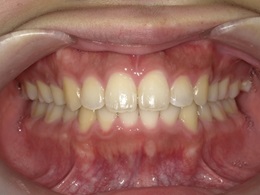

治療前正面

治療後正面